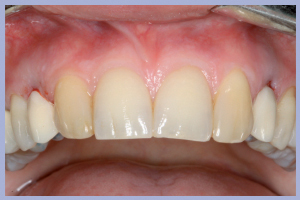

I successivi passaggi portavano all’allestimento dei manufatti definitivi in zirconia-ceramica. In particolare venivano allestite tramite procedura CAD-CAM delle cappette in zirconia da incollare sui monconi per ottenerne una individualizzazione estetica; sempre con procedura CAD-CAM si ottenevano le strutture in zirconia successivamente ceramizzate per ottenere i manufatti definitivi (Figg. 23-25).

La consegna dei manufatti a supporto implantare veniva effettuata previa cementazione extra-orale degli stessi (Figg. 26-28).

La valutazione clinica al momento della consegna dei manufatti e clinico-radiologica a 3 mesi dalla consegna manifestava una completa integrazione tissutale con eccellente recupero estetico e funzionale (Figg. 29-30).

- Fig. 26 – Cementazione extra-orale dei manufatti

- Figg. 27a, b – Consegna dei manufatti

- Figg. 28a, b – Confronto tra inizio e fine trattamento